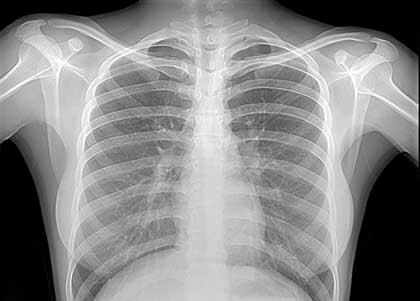

Чтобы правильно определить вид спондилеза и назначить верное лечение, нужно вначале пройти диагностические процедуры. Врачи в первую очередь назначают:

- Рентген. Он позволит увидеть наросты на позвоночнике, их точный размер, форму и месторасположение. В момент лечения рентген позволяет следить за процессом выздоровления;

- МРТ. Эта диагностика стоит дороже. Она позволяет точнее увидеть стадию заболевания, определяет до миллиметра размер нароста;

- Компьютерная томография. Показывают необходимую информацию по болезни. Стоит дешевле, чем МРТ.

После определения особенности болезни и стадии спондилеза, врач назначает точное лечение.

Рентгенография — показывает костные наросты, утолщение суставов и сокращение расстояния между позвонками, МРТ — визуализирует мягкие ткани, показывает наличие компрессии нервных структур, КТ — дает информацию о наличии стеноза, или сужения позвоночного канала.